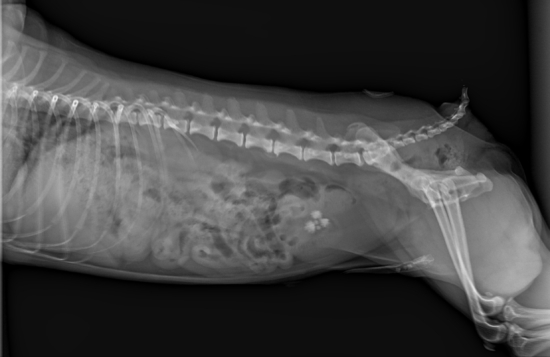

次にレントゲン検査です。レントゲン検査は胸部撮影が基本です。胸部レントゲンでは、心臓の大きさや形態が大まかにわかります。肺に病変がないか?なども確認します。他にも胸腔内を走行する血管や気管などを確認することが出来ます。全身麻酔は、循環機能を低下させ、呼吸機能も低下させますので、重度に心臓機能が低下したり、肺機能が低下している症例に対して、全身麻酔を行った場合に、麻酔時間に関係なく危険であることは明白です。特に猫の肥大性心筋症などでは注意が必要です。次の写真は肥大性心筋症の写真です。